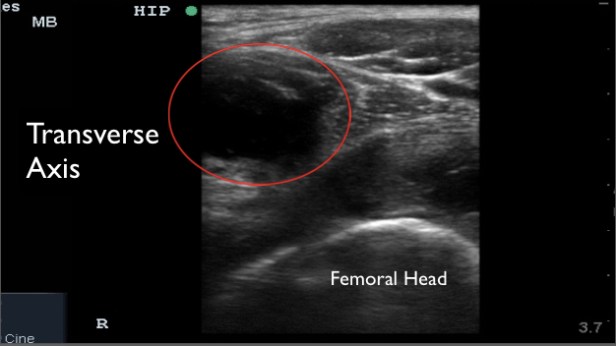

A large mass like collection was identified in this patient. It was initially assumed to be a large joint effusion, but on further evaluation it was less clear if the collection was within the joint capsule or just outside the capsule. I believed the collection was just outside the joint and likely pyomyositis. A radiologist at the bedside believed it was most likely within the hip joint.

Surgery was re-consulted post imaging and they recommended ultrasound guided diagnostic fluid aspiration.